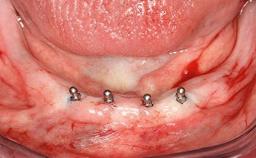

Improving an Existing Implant-supported Denture in an Alzheimer Patient with Bipolar Affective Disorder with Moderate Depression and Dementia

An 83-year-old man presented together with his caregiver at the dental department of the Medical University of Innsbruck, Austria with complaints of swelling in the right maxillary canine area and loss of retention of his 5-years-old mandibular denture. The patient had a significant medical history (20 years) of bipolar affective disorder with moderate depression (F 31.3) and dementia in Alzheimer’s disease (F 00.2). The patient had been in ambulant psychiatric therapy for his depressive illness for the past 20 years. He lived alone and had no children; his sister assisted with daily living. She reported that the patient exhibited compulsive hoarding behavior. In the previous two months, she had noted increasing disorientation and vertigo in the patient. She therefore accompanied him for a medical consultation at the Department of Psychiatry and Psychotherapy of the Medical University of Innsbruck. He was released home after a 6-week inpatient stay.

# of Implants 2

Type of Implants One-Piece

Defining Characteristics Fully edentulous lower jaw to be rehabilitated with two or more implants

Modality 2 interforaminal implants

Bone Volume Horizontally and vertically sufficient